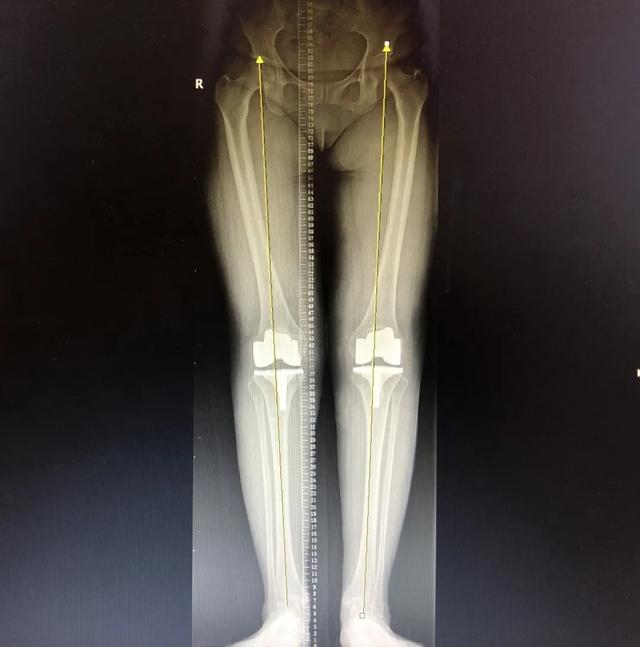

术后第二天,冯阿姨在骨科刘克宇副主任医师和周平主治医师指导下,进行了直腿抬高、屈膝深膝等康复护理及助行器下康复锻炼。6 天后,骨科团队和麻醉团队再次成功为冯阿姨实施了「右侧人工膝关节置换术」。

术后